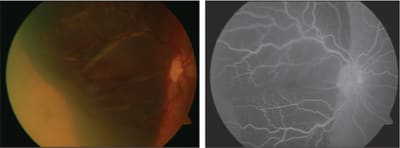

A prospective randomized study comparing FMT and PDT in subfoveal classic CNV recently showed the superiority of FMT in terms of visual gain (see before and after images in Figures 2 and 3). In spite of postop complications and the disturbed binocular vision, the reading VA and the quality of life of many patients improved.3

Figure 2. Color and fluorescein image with massive submacular hemorrhage in single-eyed patient, visual acuity hand motions.